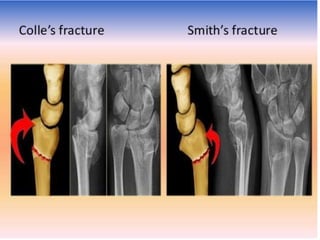

Colles Fracture

Colle’s fracture-

• Radius gets fractured about 2 cm above its lower end

due to fall on outstretched hand

Smith’s fracture- Reverse of Colle’s fracture

• If distal fragments gets displaced anteriorly

Smith Fracture

Colle’s fracture- • Radiusgets fractured about 2 cm above its lower end due to fall on outstretched hand Smith’s fracture- Reverse of Colle’s fracture • If distal fragments gets displaced anteriorly